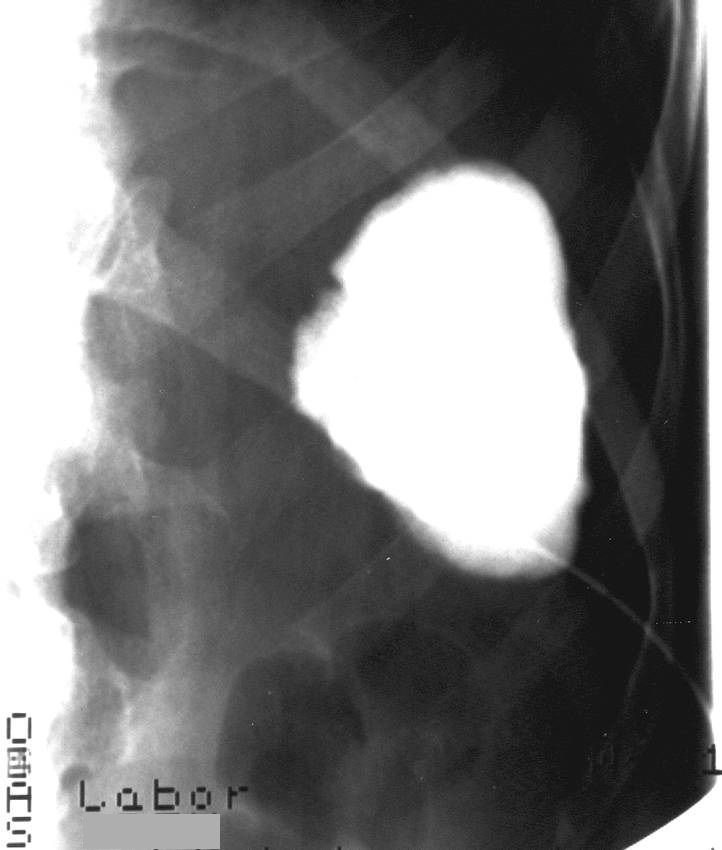

14.1.1.7. Percutaneous transhepatic cholangiography (PTC)

The percutaneous contrast filling of the biliary ducts can be necessary if no reassuring diagnosis was made by US, CT or MRI scans, or the ERCP implementation was unsuccessful due to a technical obstacle (Billroth II. gastric resection, choledochojejunostomy), or the canulation of the papilla of Vater was technically failure. PTC can be only performed in case of appropriate bleeding or coagulation status. (Figure 9) .

Figure 9: PTC (Percutaneous transhepatic cholangiography)

Significant amount of free abdominal fluid is also a relative contraindication. In the course of PTC, the liver punction is usually performed in the 9th or 10th rib spaces under fluoroscopic guidance using a 22 G Chiba needle. The punction should be guided towards the liver hilum. US guidance is helpful in the easier puncture of dilated or even peripherially located biliary ducts. The entire biliary system can be filled through this puncture. Following the diagnostic biliary duct contrast administration – after a previous consultation – bridging of the detected biliary stenosis can be performed (PTC-PTD, biliary duct stenting). Moreover, percutaneous stone extraction can be carried out if necessary.